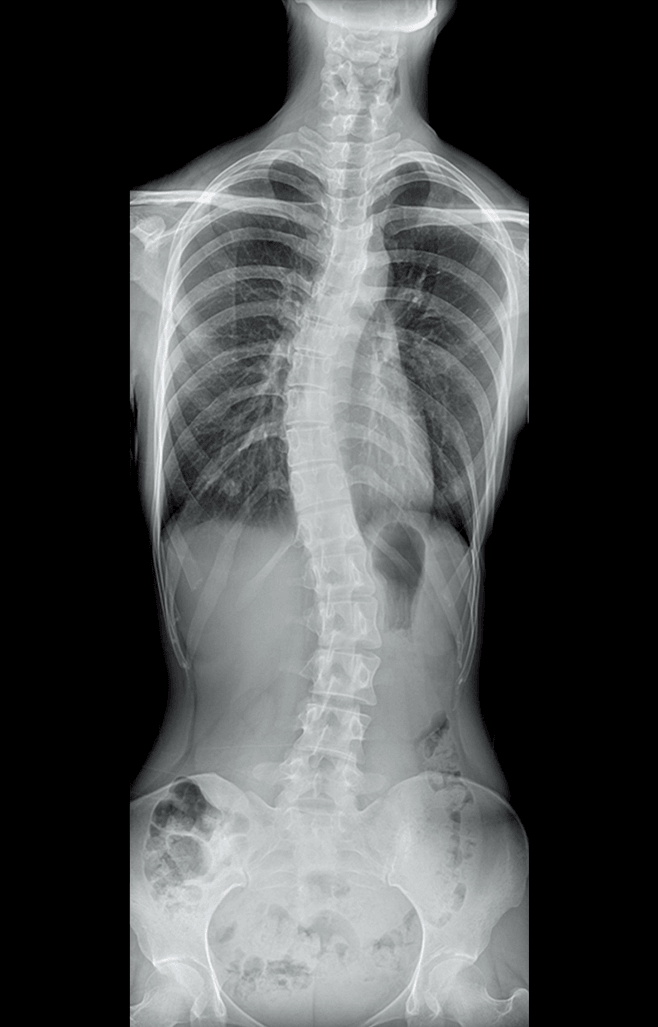

多功能诊断专用动态DR

太阳成集团tyc122cc入口科技全新设计的第四代床式动态DR,集拍片、透视、造影、全身拼接、尘肺体检于一体,一机多能,真正意义上实现全科室应用,提升医院实际效益。

高清动态平板探测器

搭载自主研发超清大视野动态平板探测器,600微米碘化铯大幅提升X线转化效率,独特的非晶硅阵列与高速读取集成电路紧密协作,轻松实现多帧率透视与高清点片。

专业的影像处理系统

“腾灵”系列搭载的IEAE影像处理系统,具备多项发明专利。本系统采用多频域图像处理技术,其6大核心处理模块使影像具有优秀的一致性、柔和性、空间层次感和纹理细腻度,为用户精准诊断病灶奠定了坚实的基础。